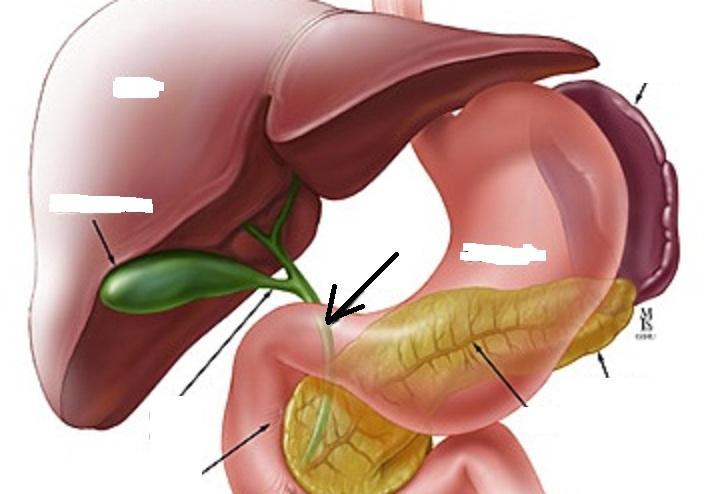

(Common) Hepatic Duct

Common bile duct

Common hepatic artery

Cystic duct

Duodenum

Gall bladder

Hepatic portal vein

Liver

arrow

Pancreas

Pancreatic duct

Stomach